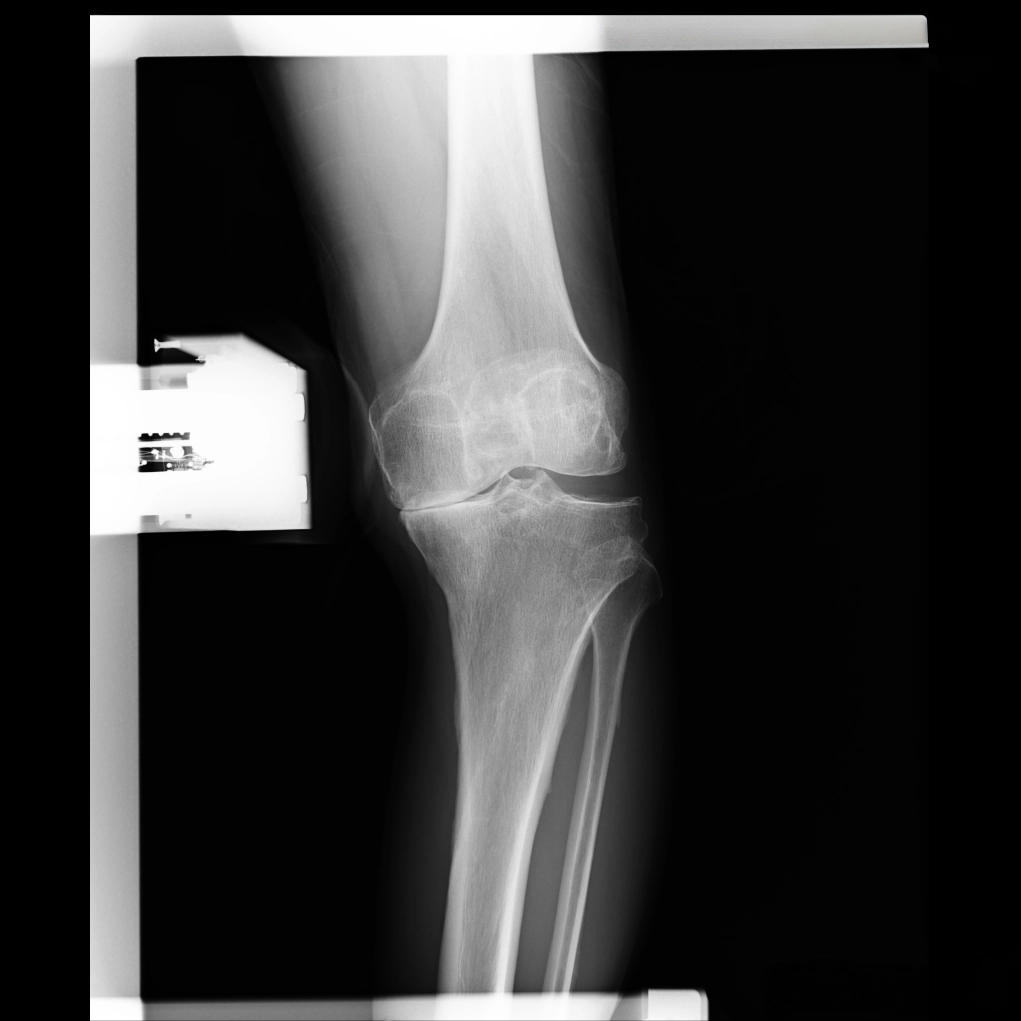

ひざ関節は、大腿骨と脛骨の間の隙間の部分です。レントゲンではこの部分が隙間として写りますが、実際には関節軟骨と半月板が存在します。立位で体重をかけて撮影した場合、この隙間の広さがおおよそ関節軟骨の厚みを示すと考えてよいでしょう。この大腿骨と脛骨の隙間のうち、腓骨に近い側を外側関節、腓骨から遠い側を内側関節と呼びます。また、脛骨の中央には2つの小さな山のような部分が見えますが、ここには前十字じん帯と後十字じん帯がついています。

※レントゲン画像左が内側、右が外側

O脚変形がみられる場合、初期のレントゲンでは外側関節に比べて内側関節の隙間がやや狭くなっています。これは内側の軟骨が少し減ってきた状態を示しています。

中期のレントゲンでは、内側関節の隙間がほとんどなくなります。この段階では、内側の軟骨が完全に失われ、大腿骨と脛骨が直接ぶつかっている状態です。低い椅子から立ち上がる際にゴリゴリという音がしたり、骨表面に髪の毛ほどの細いひび(微小骨折)が生じて強い痛みを感じるようになります。この中期変形性関節症の時期になると、痛みのために歩くのがつらくなる方が多くなります。

末期では、脛骨がすり減り、大腿骨がめり込んだ状態になります。ここまで変形が進むと、ひざの中にある4つの靱帯のバランスも悪くなり、歩行が不安定になってしまいます。